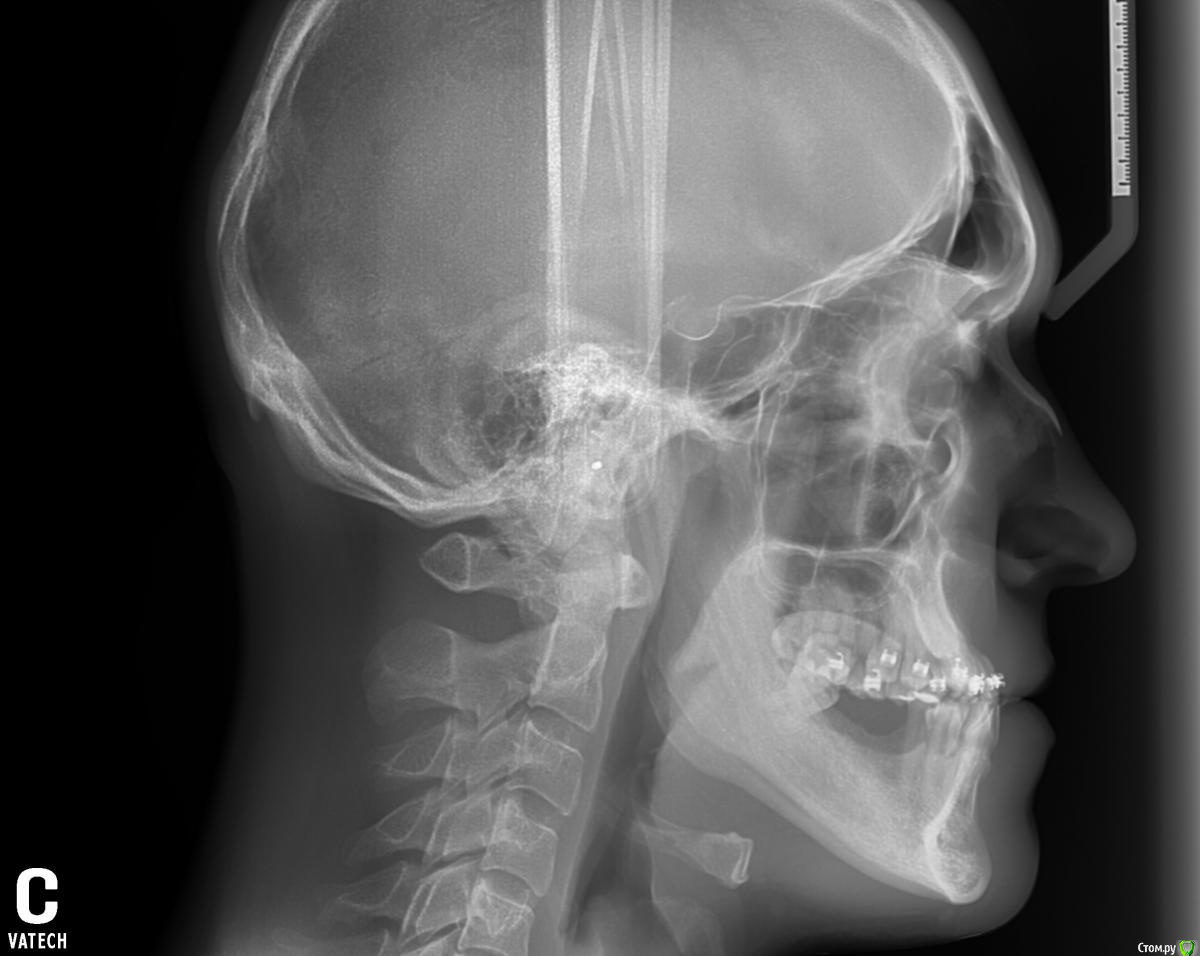

Jeniaspb Опубликовано 20 июля, 2015 Поделиться Опубликовано 20 июля, 2015 Пациент 32 года. Фото к сожалению только те, что есть. По ТРГ верхняя микрогн и нижняя прогнатия, протруз резцов в/ч 132^ и ретрузия резцов н/ч 68^, а так же переднее положение головки н/ч. Идеально сделать гнатич хирургию, но пациент идет в полный отказ, в связи с чем имеются следующие мысли:1) провести ТЭНС терапию с определением положения н/ч, в надежде на то, что она сместится хоть чуточку назад.2) если н/ч сместится каппа на н/ч с последующ окклюз накладками3) б/с на нижн зубн ряд и попыткой смещения дистально премоляров для освобожд места резцам4) б/с на в/ч и попытки камуфляжа этого всего...5) имплантация и затем протезирование.Вопрос самый главный:на сколько велики мои шансы сделать обратное перекрытие, которое я не смогу вернуть?) Ссылка на комментарий